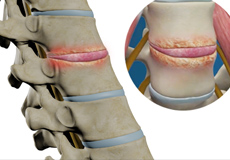

Herniated Disc (Lumbar)

Herniated disc is a condition in which the outer fibers (annulus) of the intervertebral disc are damaged causing the soft inner material of the nucleus pulposus to rupture out of its space. A herniated disc, common in the lower back (lumbar spine) occurs when there is a tear in the outer lining of the disc (annulus fibrosus). This causes the inner jelly-like material (nucleus pulposus) to leak out and place pressure on the adjacent spinal nerve root. It is the most common cause of lower back pain and pain that radiates down the leg (radiculopathy).

Lumbar Herniated Disc

A herniated disc is a condition in which the outer fibers (annulus) of the intervertebral disc are damaged, causing the soft inner material of the nucleus pulposus to rupture out of its space. It is the most common cause of lower back pain and pain that radiates down the leg (radiculopathy).

Lumbar Disc Herniation

Lumbar disc herniation is the most common cause of lower back pain and leg pain (sciatica). Aging, injury or trauma may cause the annulus fibrosus to tear, resulting in protrusion of the nucleus pulposus. This may compress the spinal nerves and/or spinal canal.

Disc Herniation

Disc herniation is a condition where the central nucleus pushes through the outer edge of the disc, causing a bulge that compresses the spinal nerves.